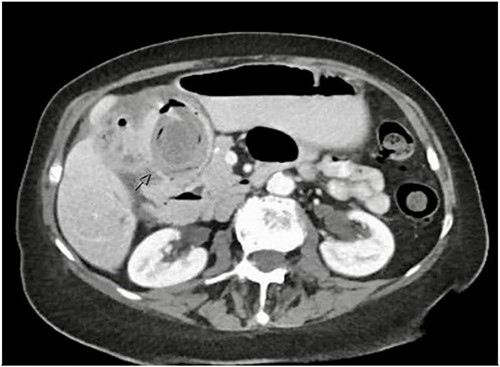

A 79-year-old female presented with a 5-day history of nausea, vomiting, and abdominal discomfort but no overt pain. She was hemodynamically stable. On examination, she had mild right upper quadrant tenderness but no signs of peritonism and a negative Murphy’s sign. Computed tomography (CT) of the abdomen and pelvis revealed features suggestive of acute cholecystitis, complicated by cholecystoduodenal fistula with a large (3.5 cm) gallstone impacted at the second part of the duodenum (Figs 1 and 2), consistent with Bouveret syndrome. The patient was kept fasting and a nasogastric tube was inserted for gastric decompression. She underwent a gastroscopy in an attempt to remove the impacted gallstone. However, the stone could not be retrieved due to its severe impaction, most evident on the pylorus side of the duodenum (Fig. 3).

Axial CT image of abdomen demonstrating a fistulous connection between the gallbladder and duodenum and a large gallstone.